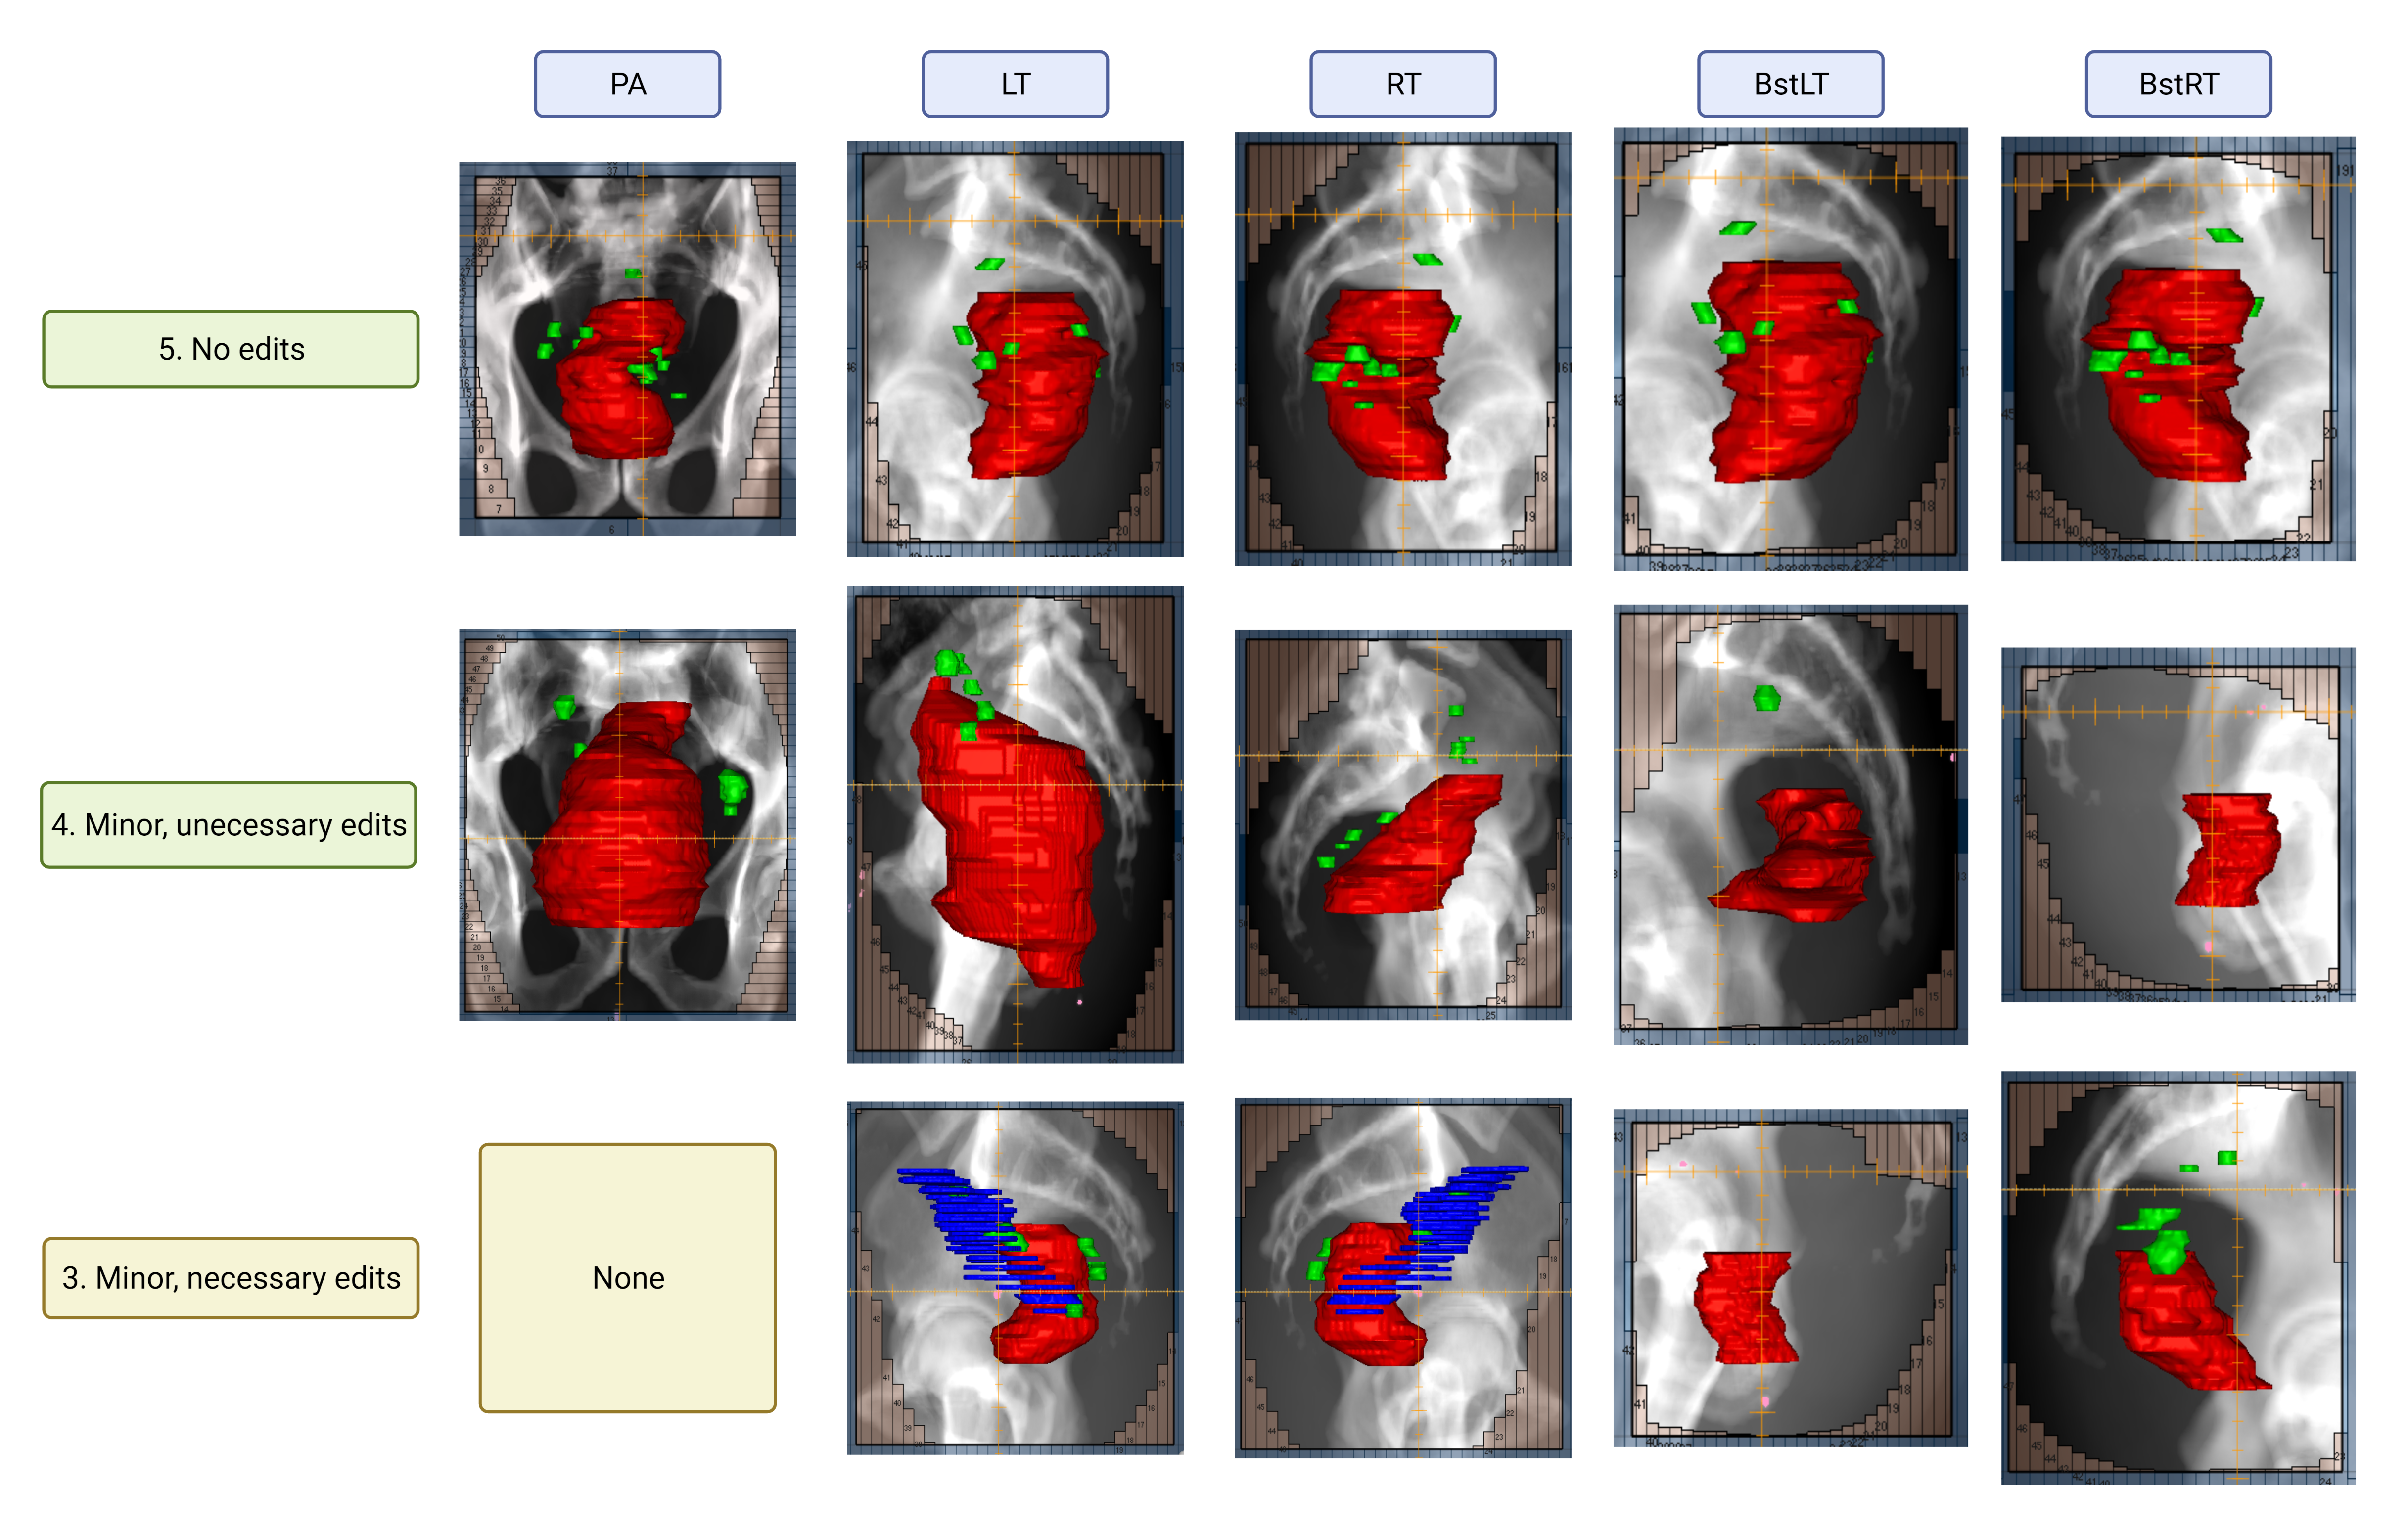

Refer to caption

Figure 5: The figure shows examples of field aperture prediction for each field at different scores.Red, green, and blue structures are gross tumor volume (GTV), involved lymph nodes (GTVn), and non-diseased lymph nodes, respectively. The non-diseased lymph nodes were included due to naming error and caused the predicted aperture to have larger anterior opening than desired.

Figure 5 shows examples of field aperture prediction after MLC fitting for each field at different scores. All primary lateral fields were rated as acceptable except for one needing minor edits because of the inclusion of noninvolved lymph nodes due to an error in structure naming. Each aperture was scored separately for each patient (a total of five apertures per patient); therefore, sometimes apertures for the same patient did not receive the same score. The most common reason for rating boost fields as unacceptable was excessive coverage in the anterior direction.